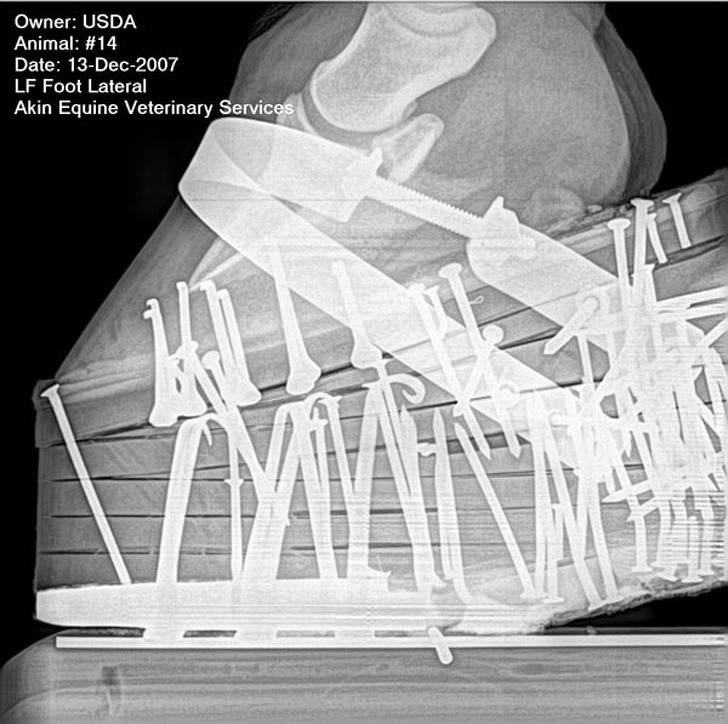

1. Guốc ngựa chứa 48 chiếc đinh

Những chiếc guốc ngựa được đóng cố định vào chân những con ngựa trong các cuộc đua. Môn thể thao này được coi là tàn nhẫn và đã bị cấm ở nhiều quốc gia bởi vì nó gây ra sự khó chịu về thể chất và tinh thần cho ngựa.